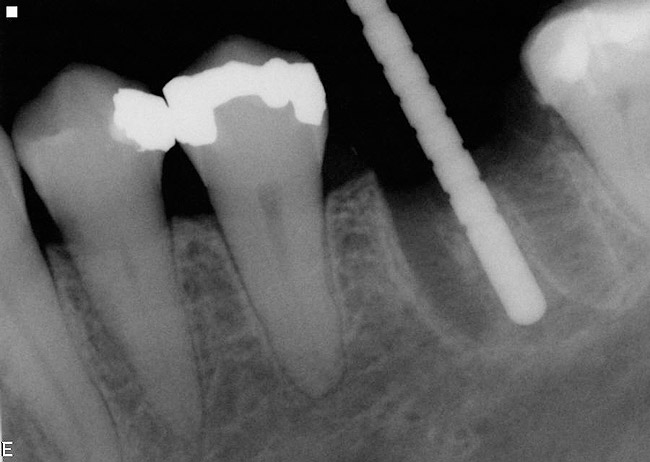

Figure 1  An implant has been placed in the mesial root socket at the time of mandibular molar extraction. The subsequent restoration demonstrates a significant cantilever and is not conducive to effective home care efforts.

Figure 1

3. Extraction of a hopeless mandibular molar, defect debridement, and placement of an implant in one of the root sockets, followed by restoration with a molar-sized crown. This approach addresses the concern of two implants being placed closely together in the root extraction sockets. However, this treatment appropriately results in a mesial cantilever of the implant restoration and an area of potential plaque accumulation (Figure 1).